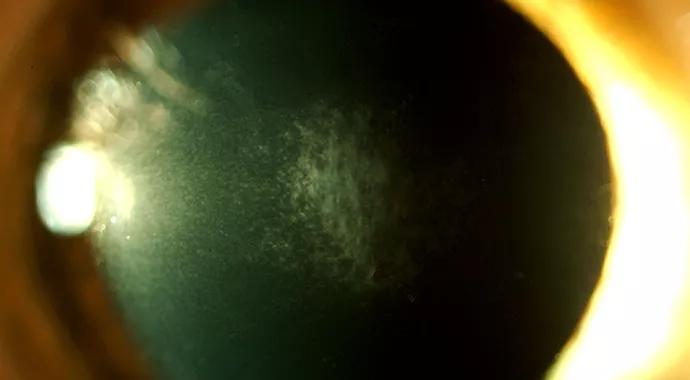

eye corneal scarring

Figure 1. Slit lamp photo of a cornea with haze at 3 months after PRK with myopia. 40X.